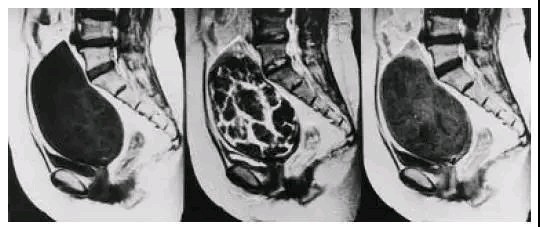

MRI的图像,不仅能从二维平面上直观的显示,还能结合其他的角度清晰的定位,图中红线部分为同一个子宫肌瘤

除了提供肌瘤的位置外,MRI还可以提供给我们很多别的信息,通常一个方向的T2加权序列会给我们提供大概26张甚至更多的图像,足够完整的显示子宫不同层面的情况,以及和周围的肠道、膀胱等组织脏器的关系,并且通过在T2加权下子宫肌瘤和子宫肌层信号的差异,能够初步判断这个子宫肌瘤是否适合我们目前开展的磁波治疗,如果是高信号(表示组织本身含水丰富或者血供丰富),那么做磁波治疗效果可能就不会太高,自然选择其他的方式就会更合适。

左图为T2低信号肌瘤,适合磁波治疗,

右图为T2高信号肌瘤,若是做磁波治疗,可能效果不佳